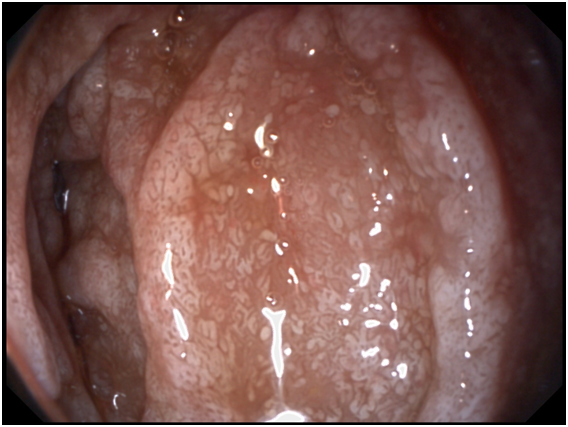

A 53- years old male presenting with chronic diarrhea of 8months duration, his diarrhea was of large volume, frothy in nature with foul odour. It was not related to a specific type of food, persisted during fasting with no diurnal variations. His condition was also associated with significant weight loss. The condition was associated with low grade fever and arthralgia of his both knee and hip joints. After 2months from the onset of his diarrhea he started to develop dizziness and easy fatigability. Physical examination of the patient was unremarkable apart from the pallor. Work up for diagnosing the cause of his diarrhea was done in the form of repeated stool analysis and culture, complete blood count, liver profile, renal profile, electrolytes, ESR, B2 microglobulins, virology (HIV, HBsAg, antiHCVab) and thyroid profile. All the previously mentioned investigations were normal apart from microcytic hypochromic anemia due to iron deficiency with haemoglobin=7.3mg/dl, serum Fe was 10mg/dl and transferrin saturation was 5%, also he had mild hypoproteinemia with serum total protein of 6.2g/dl and mild hypoalbuminemia with serum albumin of 3g/dl. His ESR was 123 and C-reactive protein (CRP) was 49mg/dl as shown in Table 1. Abdominal ultrasound was completely normal. Attempts of giving empirical medications in the form of metronidazole and quinolones failed to control the condition of the patient. Endoscopic intervention was decided in the form of upper endoscopy and colonoscopy. Total colonoscopy and terminal ileoscopy were done with no abnormality detected. For the upper endoscopy; the duodenal mucosa down to the proximal jejunum was markedly congested with extensive whitish mucosal patches as shown in Figure 1-3. Multiple biopsies were taken; histopathological examination showed focal villous distortion and focal villous erosions. The lamina propria showed mild mono-nuclear cell infiltrate with extensive infiltrate of foamy macrophages with dilated lymphatic spaces as shown in Figure 4. PAS (periodic acid shiff) stain was applied during microscopic examination where the organism was detected as shown in Figure 5. And hence the patient was diagnosed as a case of Whipple’s disease (WD). Then treatment was started accordingly in the form of ceftriaxone for 15days followed by trimethoprim-sulfamethoxazole (TMP/SMX) twice a day for 1 to 2years with marked improvement of the patient's condition. The improvement was evident by his laboratory parameters (Table 1) and endoscopic picture (Figure 6).

Figure 1 Shaggy mucosa of the duodenum.

Diagnosis is made from duodenal biopsy, taken by upper endoscopy, which reveals pale yellow shaggy mucosa with erythematous eroded patches in patients with classic intestinal Whipple's disease25 and this is seen in our patient. Histopathological examination of the duodenal biopsies shows infiltration of the lamina propria with PAS-positive macrophages with intracellular clumps of T. whipplei.3 Immunohistochemical staining for antibodies against T. whipplei has been used to detect the organism in a variety of tissues, and a PCR-based assay is also available.26 Electron microscopy can be diagnostic showing coccobacillary bodies that represent the T. whippeli organism. Histologic examination with routine H&E and PAS stains is usually sufficient to reach a diagnosis, however, it is recommended that PAS-positive histologic findings to be confirmed with other methods when establishing the diagnosis of WD.25,26